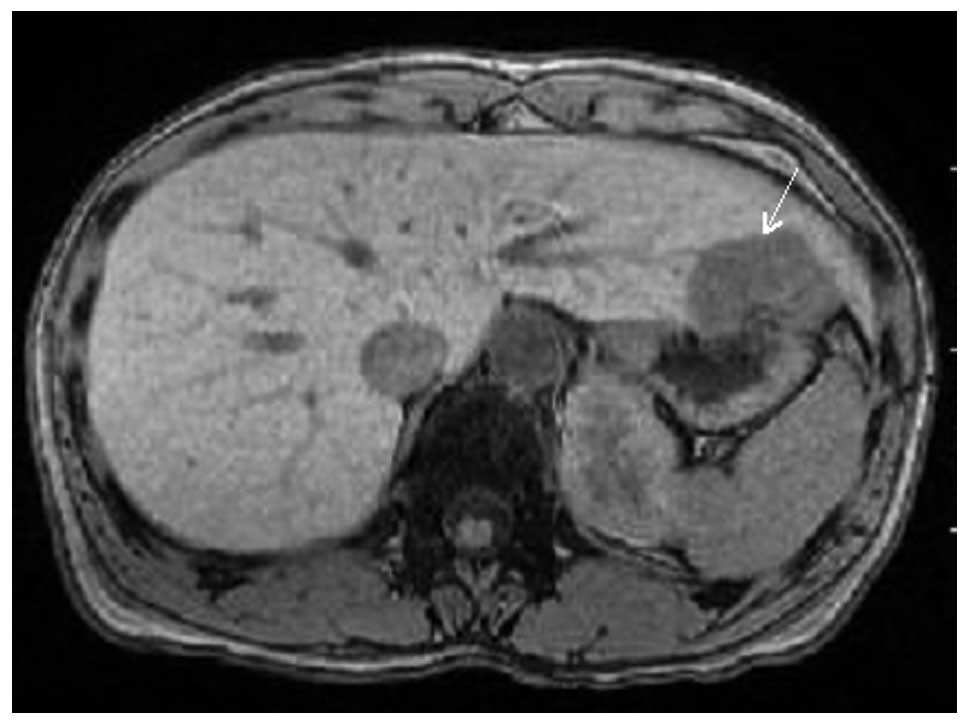

A 37-year-old Japanese female presented with a right breast tumor. A physical examination revealed a relatively well-circumscribed tumor, measuring 3×2.5 cm in diameter, in the right breast and swollen right axillary lymph nodes. No metastatic lesions with the exception of the right axillary lymph nodes were detected by computed tomography (CT). The biopsy specimen of the right breast tumor revealed invasive carcinoma; thus, total mastectomy and removal of the right axillary lymph nodes were performed (cT2N1M0, stage IIB). Chemotherapy and hormonotherapy were administered following the surgery. Three years later, local recurrence was observed on the operation scar of her right thoracic wall, and tumor resection was performed again. Seven years after the first surgery, a liver tumor was detected during the follow-up CT. CT and magnetic resonance imaging demonstrated a relatively well-circumscribed tumor, measuring 42×37×30 mm, in S3 (Fig. 1). Metastatic breast cancer in the liver was suspected clinically, resulting in the surgical resection of the liver tumor. The post-operative course was uneventful, and the patient has been free from recurrence for 18 months of medical follow-up.

Figure 1

Magnetic resonance imaging showing a relatively well-circumscribed tumor in the liver (arrow).